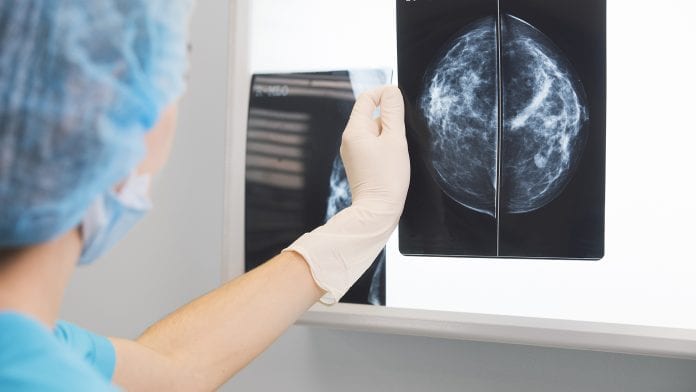

Invasive biopsies may become a thing of the past thanks to a new breakthrough in breast cancer screening.

Harnessing photonics, European scientists have created a new breast cancer screening process using mammographic imaging system that determines benign or malignant breast lesions – spelling an end for unnecessary biopsies and anguish for millions of women.

While mammography is accurate in detecting breast lesions, many women encounter false positive results – a positive detection of a lump but with no malignant cancer present.

Clinicians, however, do not necessarily know whether a lesion is cancerous or harmless and have to resort to invasive procedures, such as biopsies, to make an accurate diagnosis. According to a recent study, false-positive breast biopsies cost more than €1.85bn ($2bn) per year in the United States alone.